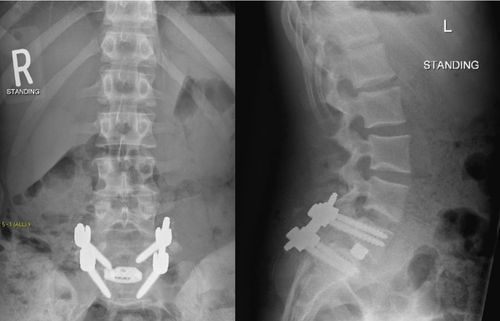

ALIF

TLIF

Posterolateral Fusion